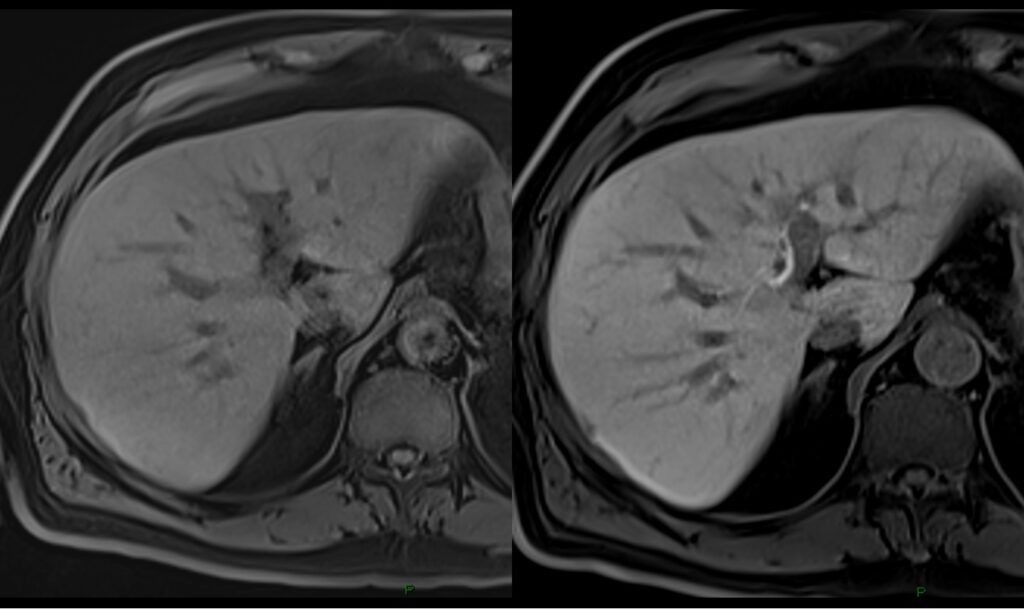

RM del fegato

Cos’è? La risonanza magnetica (RM) del fegato con mezzo di contrasto epatospecifico (MDC) è una tecnica diagnostica avanzata che impiega campi magnetici e onde radio

Mezzi di contrasto epatospecifici

Cosa sono? I mezzi di contrasto (MDC) epatospecifici sono farmaci che vengono iniettati endovena durante un esame di risonanza magnetica per lo studio del fegato,